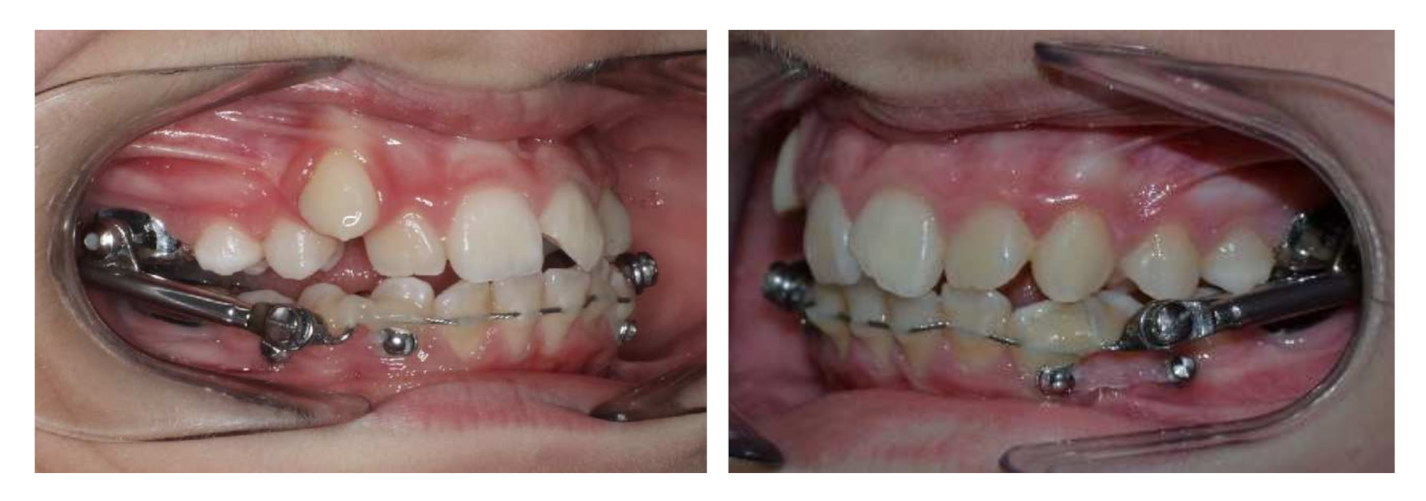

5. Treatment Progress

6. Treatment Results